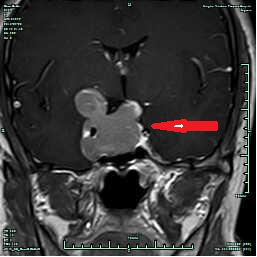

CASE1 病人***女性,36岁,因“视力下降2月”入院,入院诊断垂体大腺瘤。

在全麻下行经鼻内镜下垂体瘤切除,病人术后恢复良好,视力明显改善,术后7天出院,术后3个月复查未见肿瘤明显残留。(红色箭头提示术前肿瘤,蓝箭头提示术后复查未见肿瘤残留)